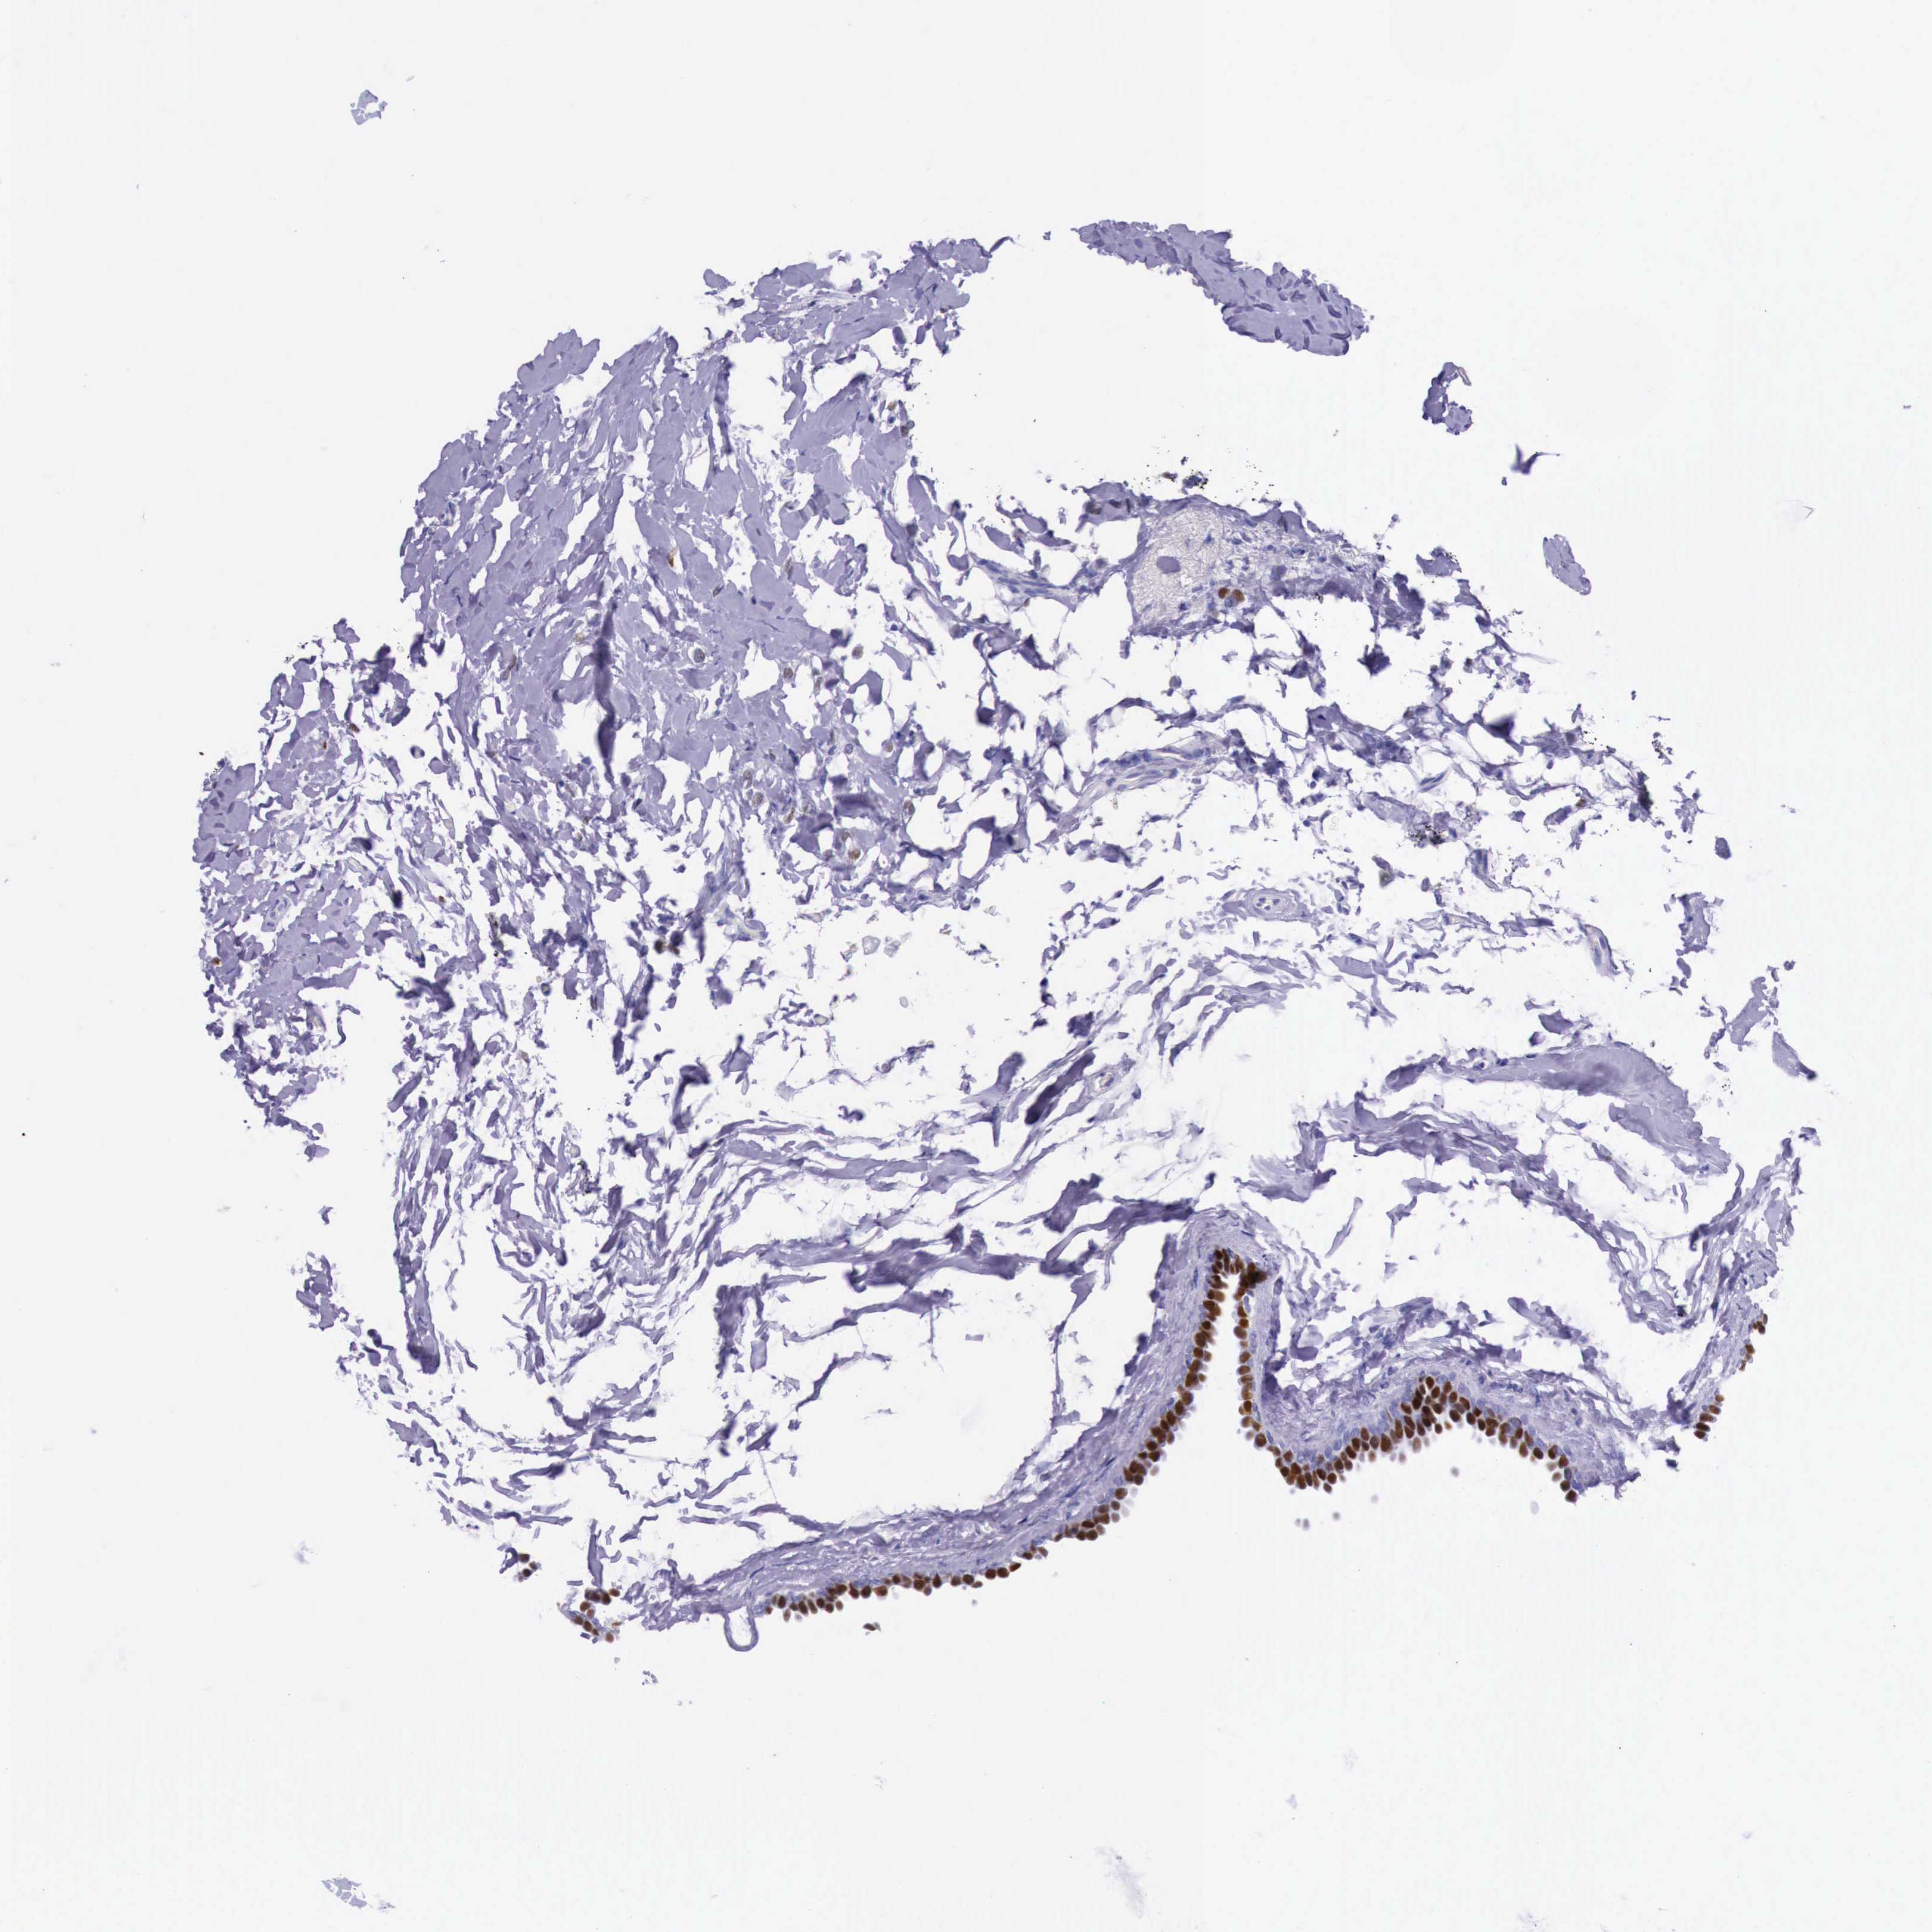

CANCER BREAST CANCER Show tissue menu

BRCA TCGA BRCA VALIDATION PROTEIN EXPRESSION

ANTIBODIES

AND

VALIDATION